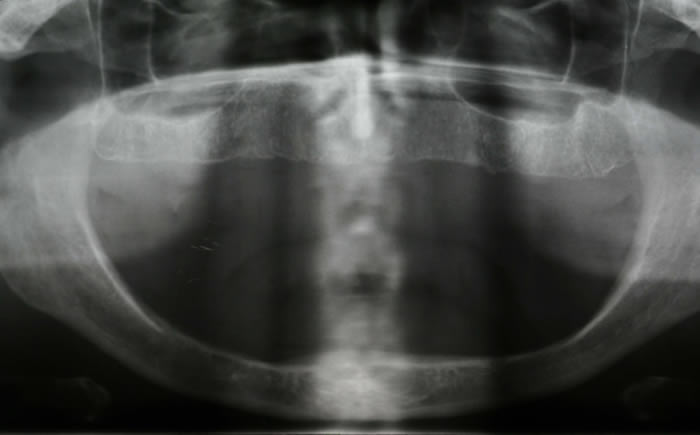

Gum disease

Case One (2 images)

Treatment of severe gum disease.